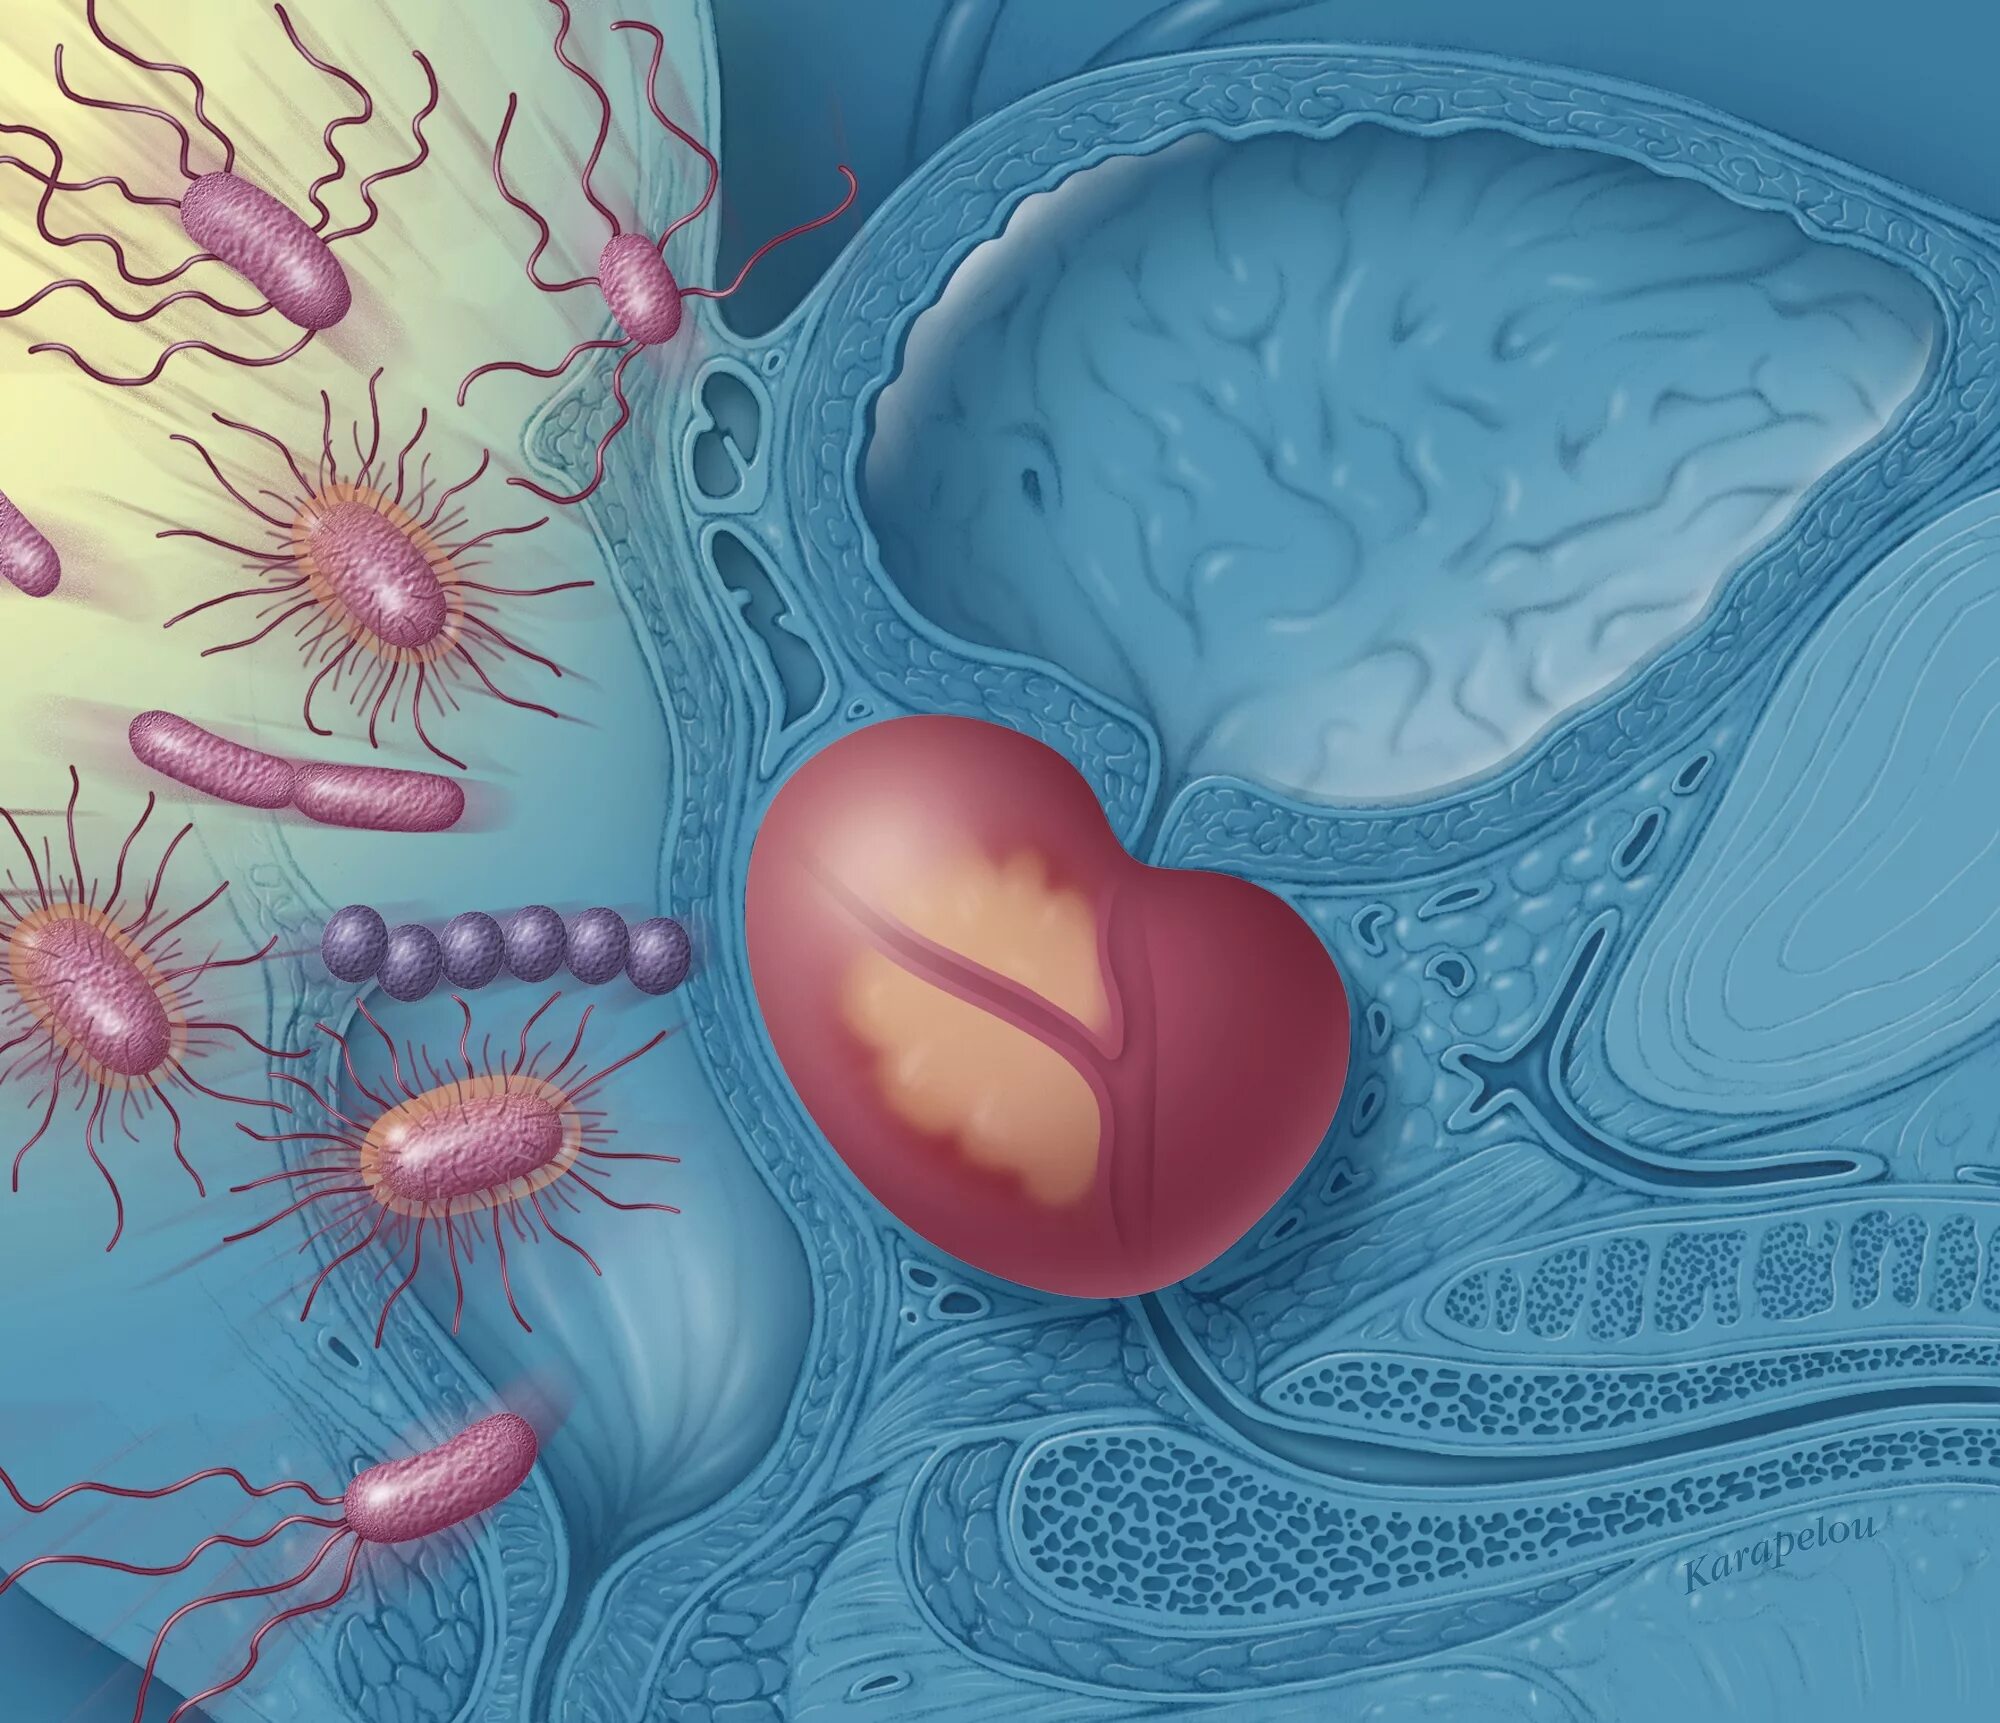

Бактериальная простата